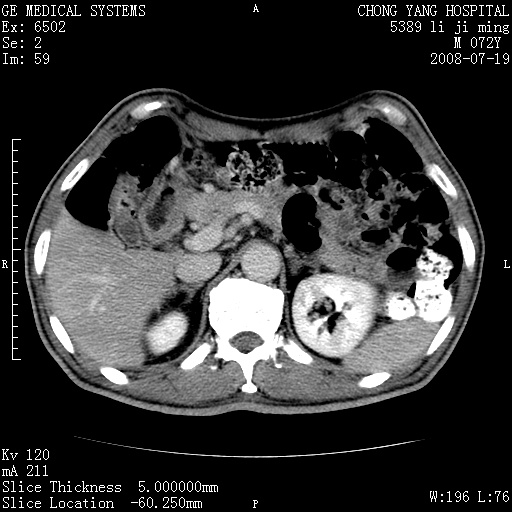

以下是引用zjzjr在2008-7-19 20:57:00的发言:[br]胰头增大,边缘模糊,周围可见渗出影,右侧肾前筋膜增厚.支持胰腺炎.

以下是引用yangyudong333在2008-7-20 6:56:00的发言:[br]胰腺增大尤以胰头明显,边缘模糊,周围可见渗出影,右侧肾前筋膜增厚,肠管於涨.支持胰腺炎

以下是引用不学无术在2008-7-19 23:15:00的发言:[br]胰腺增大尤以胰头明显,边缘模糊,周围可见渗出影,右侧肾前筋膜增厚,肠管於涨.支持胰腺炎